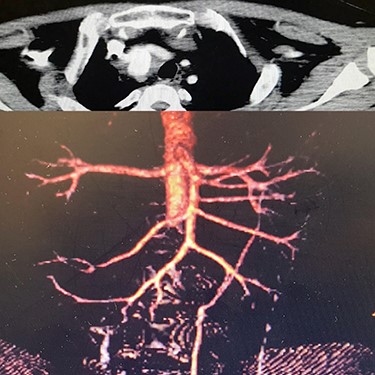

Case 4 – A 32-year-old man who was a known case of BD presented to the emergency department with a complaint of abdominal pain. In the abdominal CT scan, he had a thrombosed abdominal infrarenal aortic aneurysm (Fig. 5A). Heparin therapy was started. A huge right subclavian artery aneurysm was found in CTA (Fig. 5B). We talked to the patient about endovascular repair of the subclavian aneurysm but he refused the surgical treatment. Tablet of prednisolon (5 mg) twice a day was prescribed. In 1-year follow-up, the aneurysm size of the subclavian artery did not expand and his lower limbs were not symptomatic.

(A) Infra renal aortic thrombosis (down), (B) right subclavian aneurysm (up).